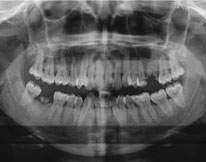

An Orthopantomogram (OPG), also known as an “orthopantogram” or “panorex,” is a panoramic scanning dental X-ray of the upper and lower jaw. It shows a two-dimensional view of the teeth and surrounding structures for a clear picture and diagnosis.

This new era dental radiography method is useful for dentists as well as patients as it saves a lot of time. It is most useful in case of doubt of the presence of cysts or tumors around the teeth or jaws. Diagnosis can be made easily, and the treatment can be started accordingly. Patient cooperation level has increased because of the ease of taking radiographs on the x-ray machine. The radiation exposure in case of the dental panoramic x-ray is around 30-40% less than that of the traditional radiograph shooting method. So, it is highly recommended instead of taking multiple radiographs according to the case.